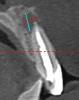

rusan Опубликовано 30 марта, 2010 Автор Поделиться Опубликовано 30 марта, 2010 Дополнительно: вот что написано в заключении канал зуба 1.1. во круг пломбировочного материала выявляется разряжение костной ткани округлой формы с четкими ровными контурами, размерами 10,2 x 6,4 - 8,4 мм..зуб 2.1 ... - 5,6x 6,7 x 4,9 мм Что посоветуйте в моем случае? Пломбировка каналов производилась несколько недель назад. Ссылка на комментарий

Bier Опубликовано 30 марта, 2010 Поделиться Опубликовано 30 марта, 2010 если у зуба нет вестибулярной костной стенки, его не сохранить. Мне к сожалению не скачать всю КТ, но по этим снимкам создается такое впечатление. Ссылка на комментарий

Bier Опубликовано 30 марта, 2010 Поделиться Опубликовано 30 марта, 2010 ну тонюсенькая костная стенка там вроде есть. Резекцию я бы не делал. Либо наступит улучшение либо удаляйте зубы с одномоментной костной пластикой. Ссылка на комментарий

rusan Опубликовано 30 марта, 2010 Автор Поделиться Опубликовано 30 марта, 2010 ну тонюсенькая костная стенка там вроде есть. Резекцию я бы не делал. Либо наступит улучшение либо удаляйте зубы с одномоментной костной пластикой. ясно. У меня сейчас такая ситуация ортодонты отказывают в лечении по причине возможных осложений (т.к. кисты и сказали что возможны осложнения при ортодонтическом лечении). Направили к хирургам (был сегодня), сказали в обязательном порядке резать, не сказав о возможных последствиях. Вопрос, в течении кого времени мне стоит сделать повторные снимки? Сейчас в зубе 1.1 чувствую неприятное немного давящее ощущение. Ссылка на комментарий